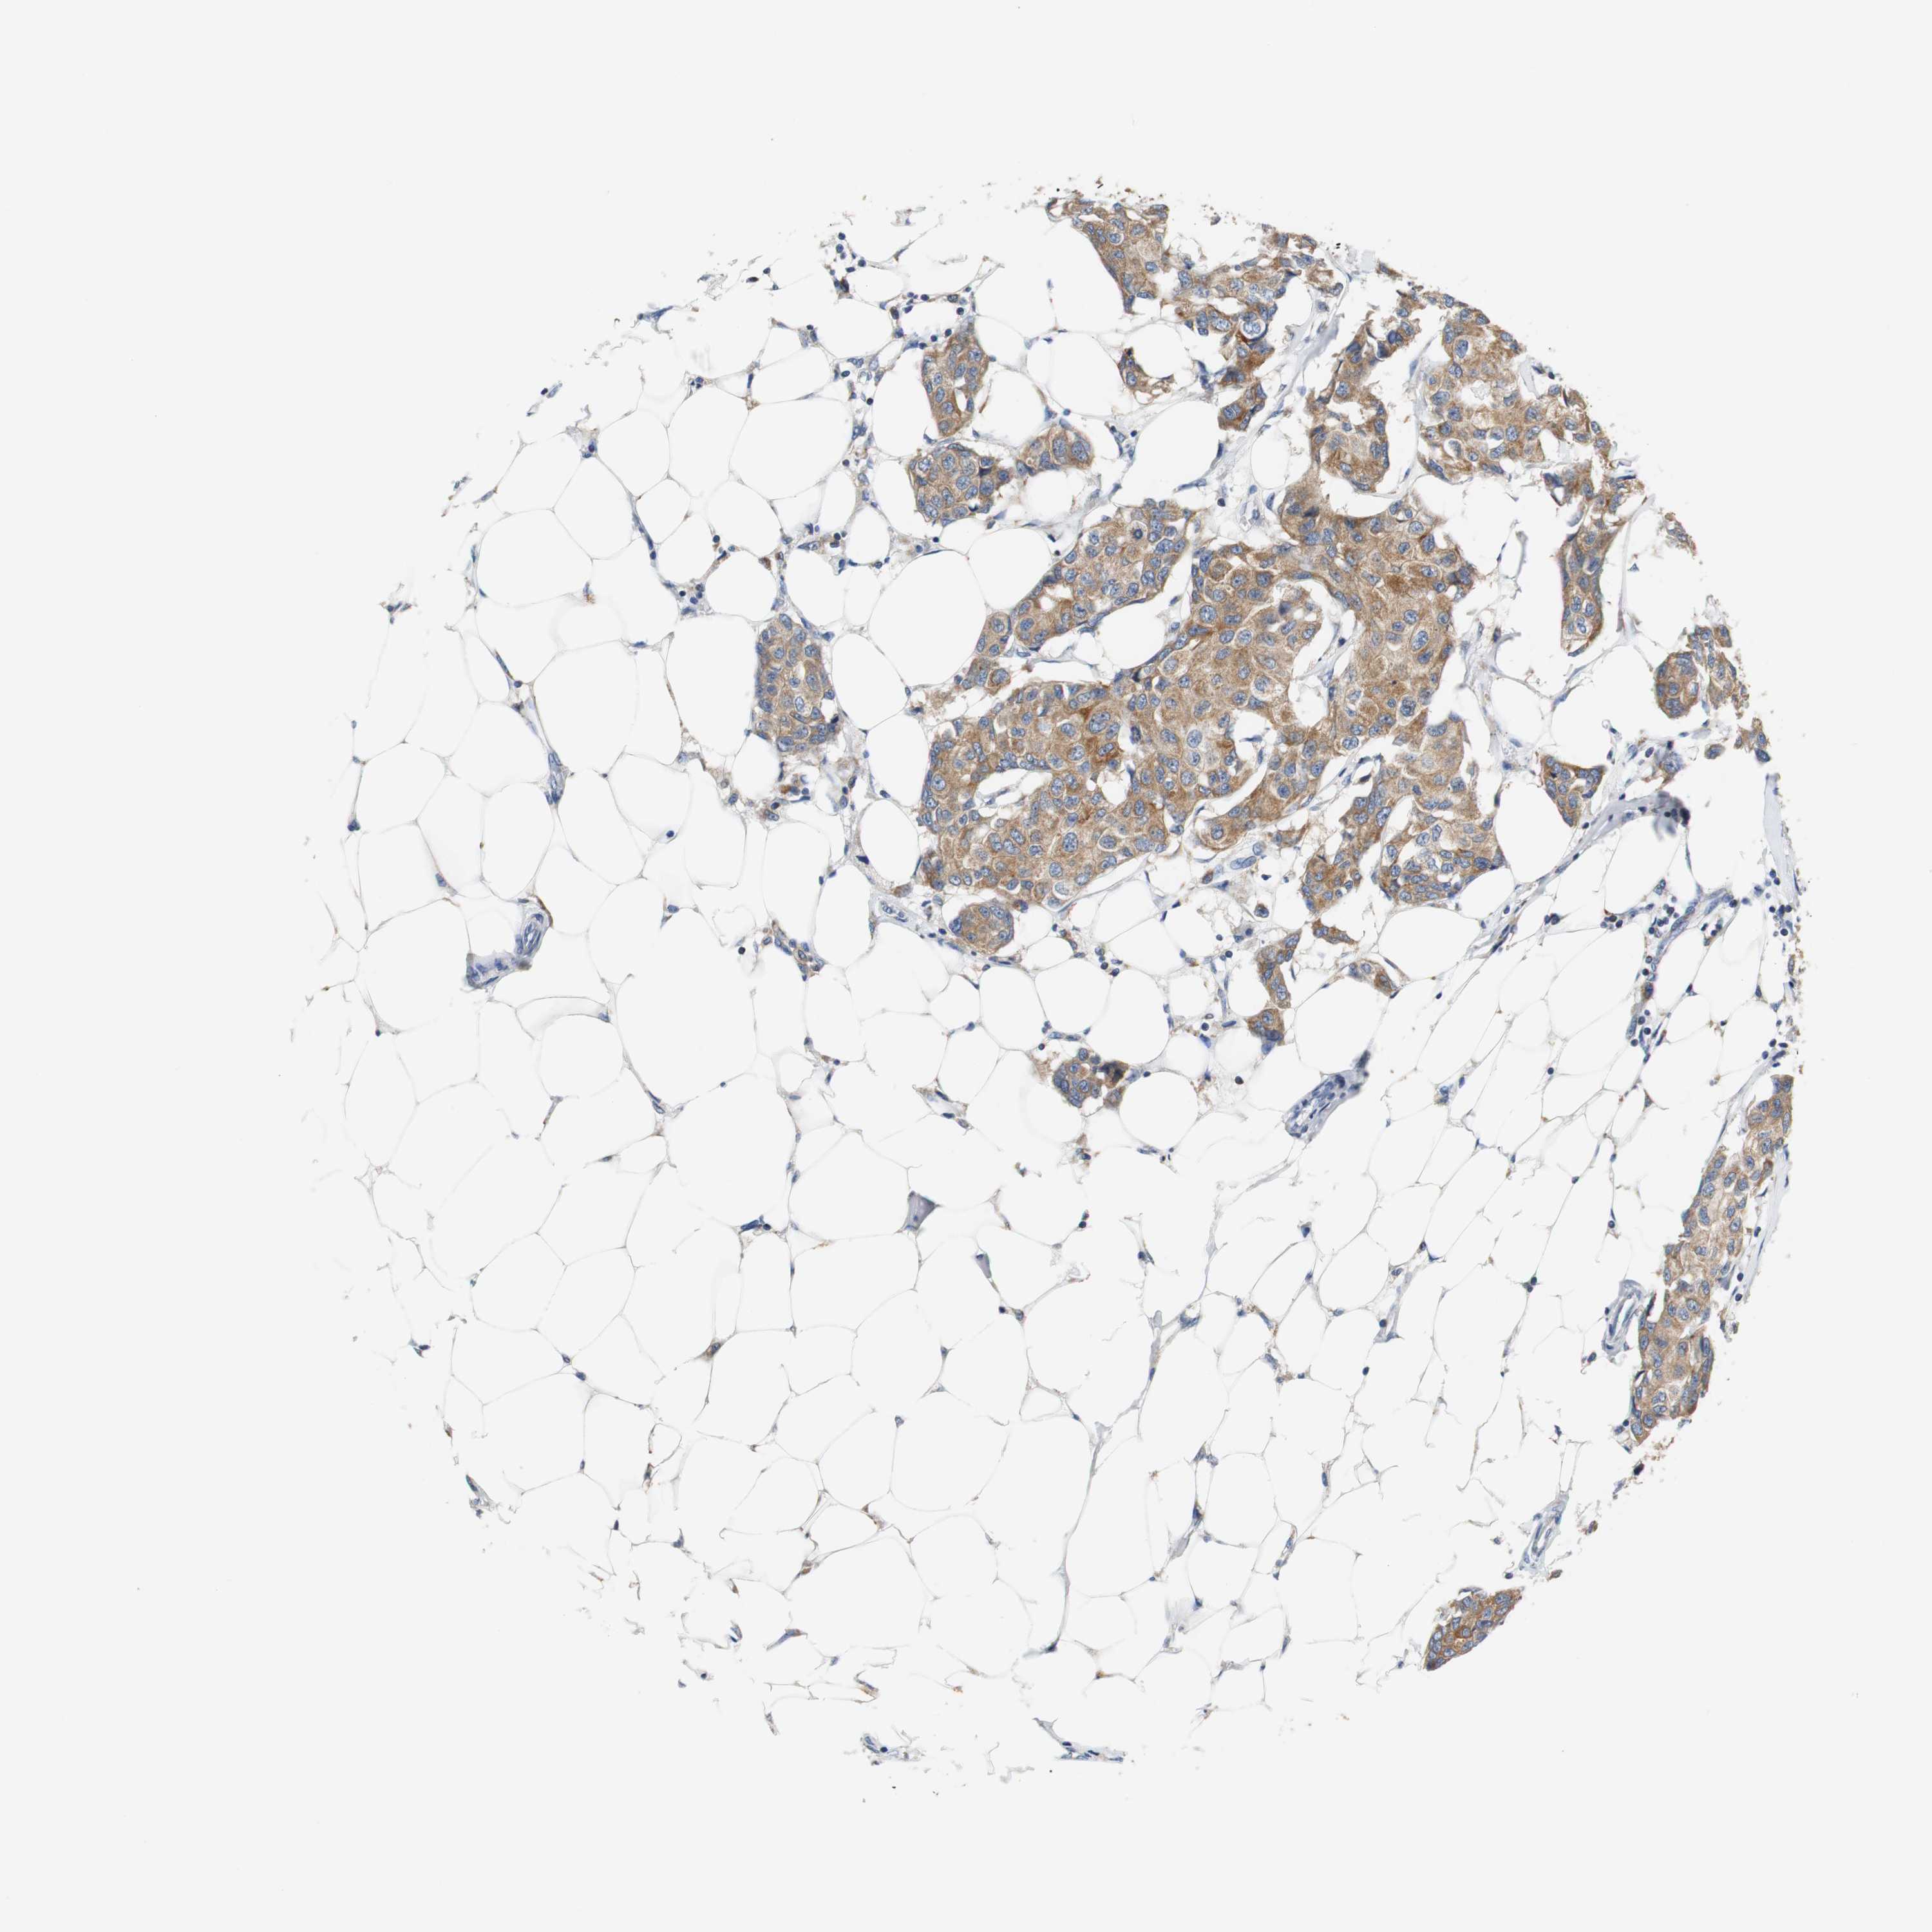

CANCER BREAST CANCER Show tissue menu

BRCA TCGA BRCA VALIDATION PROTEIN EXPRESSION